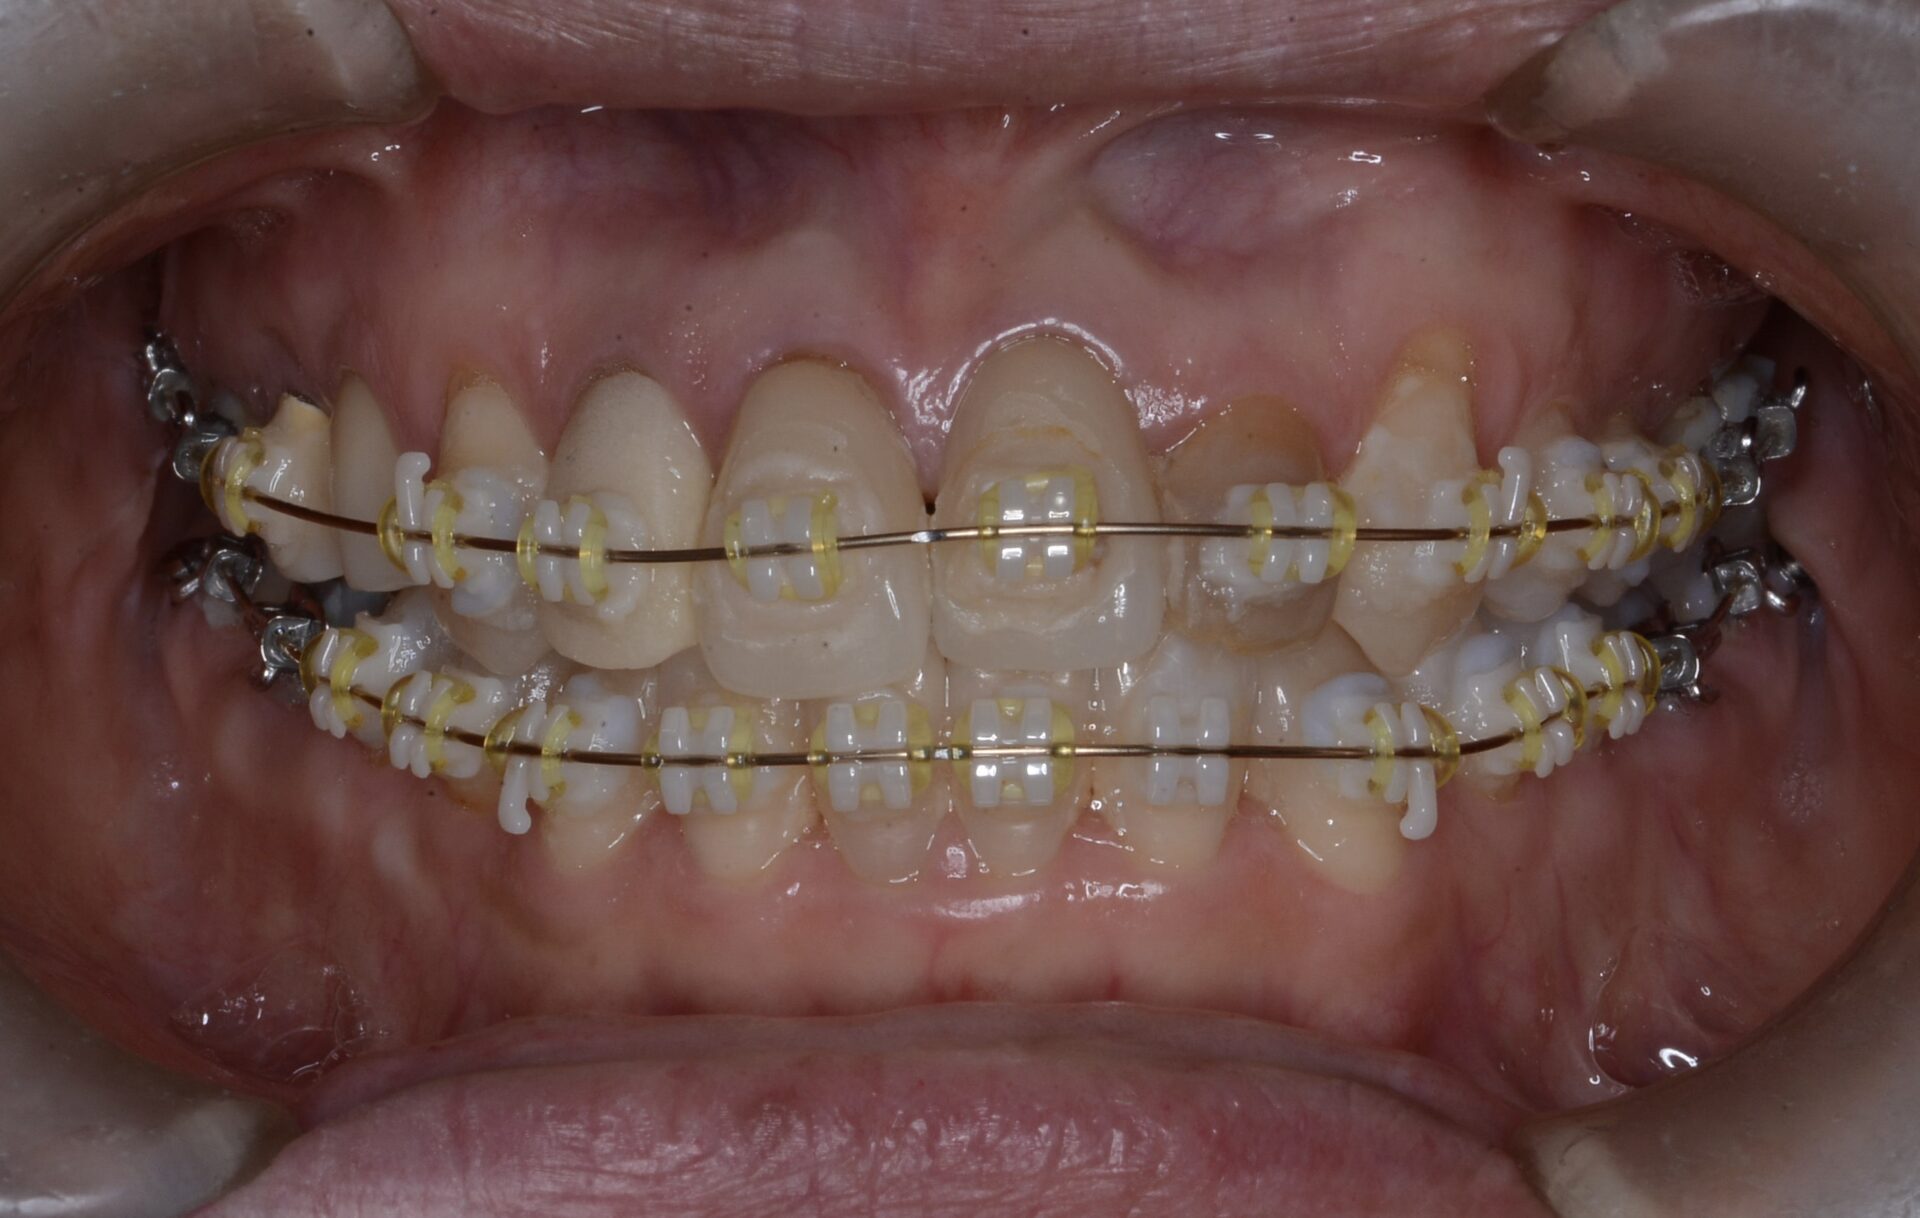

矯正治療スタート(正面)

矯正中